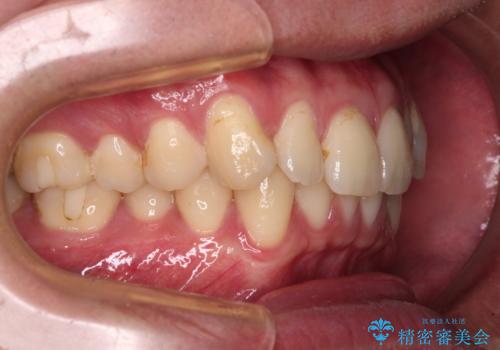

上下のデコボコを治したい インビザラインによる矯正治療

- 前歯のデコボコと突出感を気にして来院された患者様です。

極力目立たない装置を希望とのことで、インビザラインを用いて非抜歯で矯正治療を行うこととしました。

事前に親知らず4本を抜歯し、多少歯列を後方に移動できるように準備をした上で、なるべく歯と歯の間を削ることなくデコボコを解消できるように計画しました。

お仕事が忙しく、1日の装着時間は不十分となる日もありましたが、治療は順調に進めていくことができました。

途中、以前大きなむし歯で処置をした歯が痛み出し、根管治療が必要となったため、根管治療とオールセラミッククラウンによる補綴治療を行い、その後にインビザラインによる仕上げの歯列移動を行い、無事に治療を終えることができました。